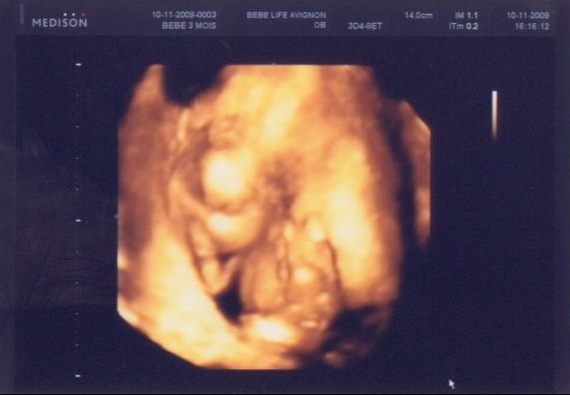

Sentir bebe 14 sa

Sentir bebe 14 saのギャラリー